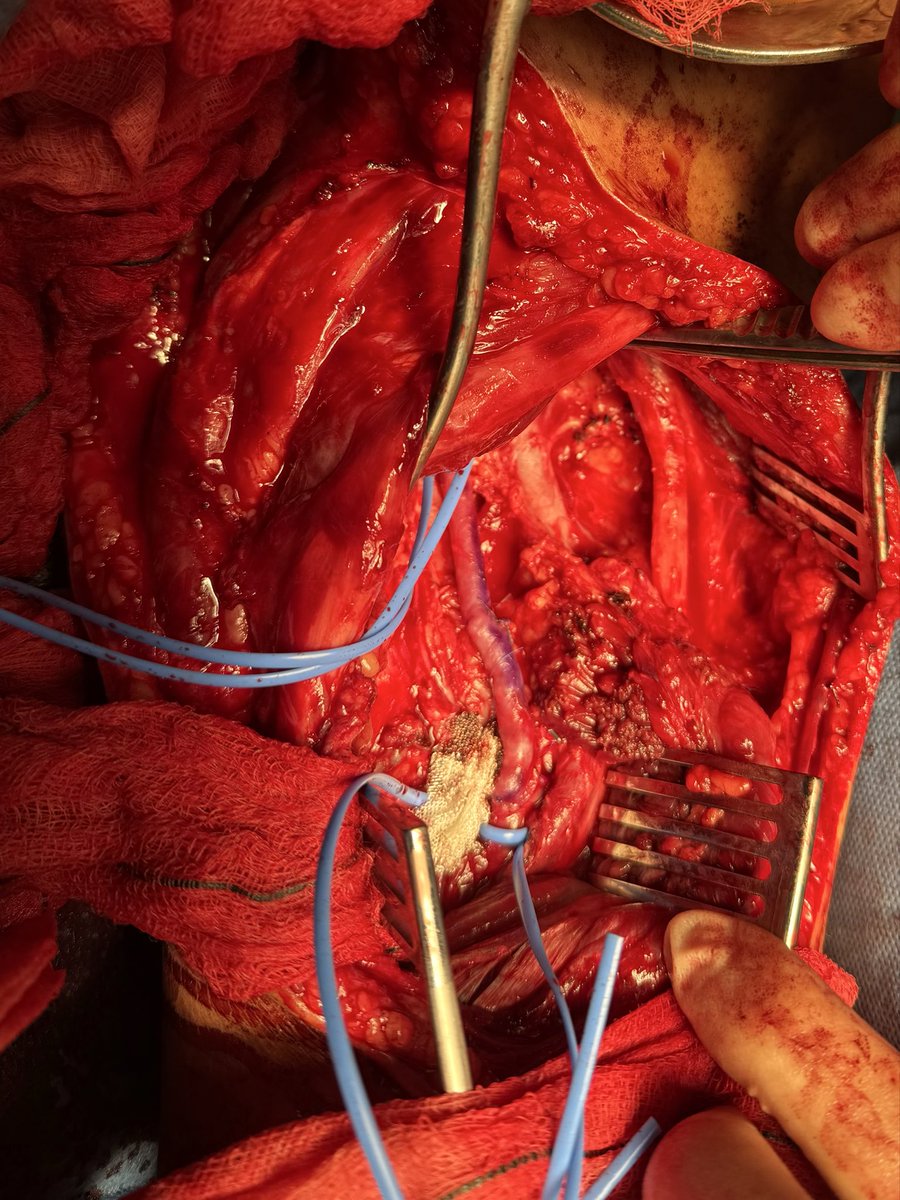

Diagnosis : Popliteal artery entrapment syndrome causing acute limb ischemia Intra-op pictures

#vasctwitter 17 yrs old male, keen football player.sudden onset pain in right leg and foot. Absent foot pulses and pale foot. CTA below. What is the diagnosis? Look at cross sectional image?! How would you treat?